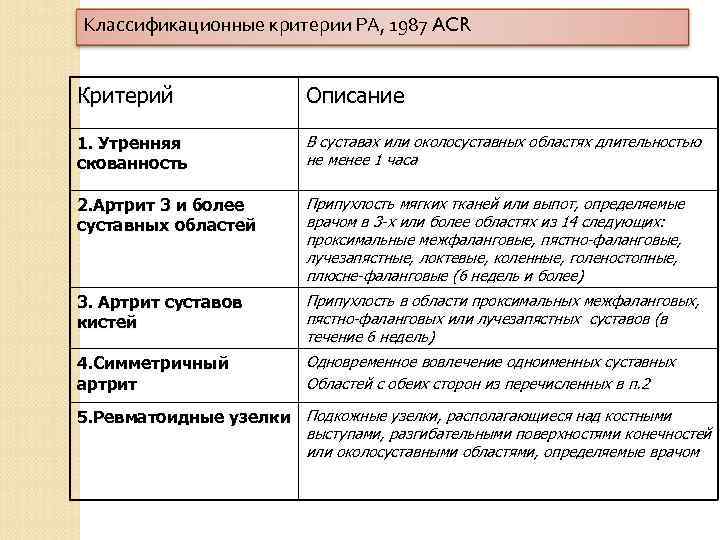

Классификационные критерии РА, 1987 ACR Критерий Описание 1. Утренняя скованность В суставах или околосуставных областях длительностью не менее 1 часа 2. Артрит 3 и более суставных областей Припухлость мягких тканей или выпот, определяемые врачом в 3 -х или более областях из 14 следующих: проксимальные межфаланговые, пястно-фаланговые, лучезапястные, локтевые, коленные, голеностопные, плюсне-фаланговые (6 недель и более) 3. Артрит суставов кистей Припухлость в области проксимальных межфаланговых, пястно-фаланговых или лучезапястных суставов (в течение 6 недель) 4. Симметричный артрит Одновременное вовлечение одноименных суставных Областей с обеих сторон из перечисленных в п. 2 5. Ревматоидные узелки Подкожные узелки, располагающиеся над костными выступами, разгибательными поверхностями конечностей или околосуставными областями, определяемые врачом

Классификационные критерии РА, 1987 ACR Критерий Описание 1. Утренняя скованность В суставах или околосуставных областях длительностью не менее 1 часа 2. Артрит 3 и более суставных областей Припухлость мягких тканей или выпот, определяемые врачом в 3 -х или более областях из 14 следующих: проксимальные межфаланговые, пястно-фаланговые, лучезапястные, локтевые, коленные, голеностопные, плюсне-фаланговые (6 недель и более) 3. Артрит суставов кистей Припухлость в области проксимальных межфаланговых, пястно-фаланговых или лучезапястных суставов (в течение 6 недель) 4. Симметричный артрит Одновременное вовлечение одноименных суставных Областей с обеих сторон из перечисленных в п. 2 5. Ревматоидные узелки Подкожные узелки, располагающиеся над костными выступами, разгибательными поверхностями конечностей или околосуставными областями, определяемые врачом